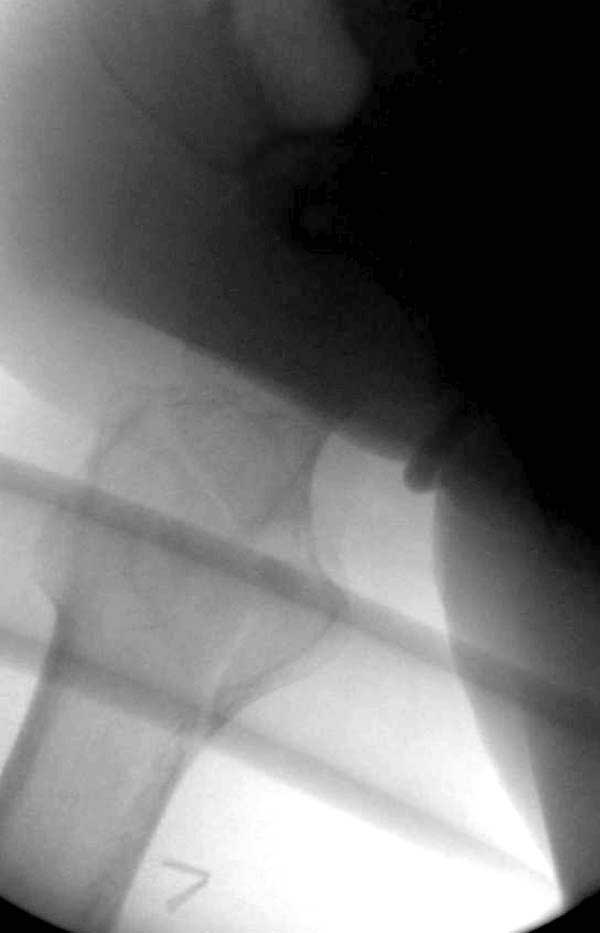

Сеньоры-пэры ревизировали гвоздем, шуруп поставили по той же дорожке, только поглубже. Да еще и bone graft не пожалели. "Результат" уже был через 2 дня.

Если сохранять головку - думаю надо было в валгусе фиксировать перелом гвоздем, или DCS, т.к. все-равно разрезали, чтоб достать DHS.

No comment.

End of story.

Неужели фиксация протеза бесцементная? Да и чашка не запрессована как надо.Грустно(

Эт -ж биполяр:)) Ножка цементная. Страйкеровский Exeter.1

биполярный эндопротез все же не лучший выбор для данной ситуации.судя по снимкам мышечные прикрепления на вертелах утрачены.Возможно здесь подошла бы более стабильная конструкция.Ваше мнение?

а куда делся фрагмент большого вертела? Очевидно,

Если среднеягодичная мышца не рефиксирована, то ничто не держит протез во впадине и это закономерный результат.

Третья операция-продолжения усилии “синьорами пэрами” по разрушению нормальной анатомии. Крест на головку! По видимому возраст позволяет биполярную конструкции, и при дефекте calcar пошли на обычный цементный. Ягодичные мышцы потеряли связь с вертелом, т.е. отсутствует верхний удержатель, и результат “a Big Screw Up!” Снимки вызывают головокружение!

Если хирурги не устали от своих “творчеств”, тогда можно ре-оперировать с calcar replacement stem, и собрать остаток ягодичных мышц. Глубина и отстутствие артроза позволяет применить любой, биполярный или тотальный, хотя принять решение можно после ревизии ацетабулума.